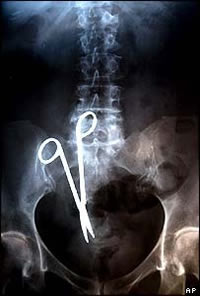

Surgical instruments left in patients and other errors

Can we assume that NHS managers have never heard about patients having the wrong leg or kidney removed or having swabs or instruments left inside them?